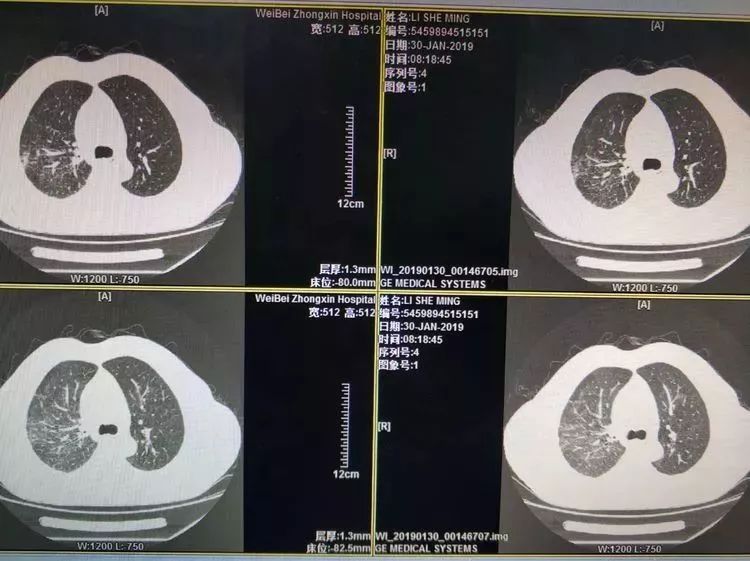

入院时胸部CT:右肺实变影,双肺渗出性改变(如下图)

入院后三天复查:WBC 11.65,中性粒细胞百分比78.40%,CRP 133.00mg/l, PCT 2.40ng/ml。胸部CT示感染较前稍有吸收(如下图)。